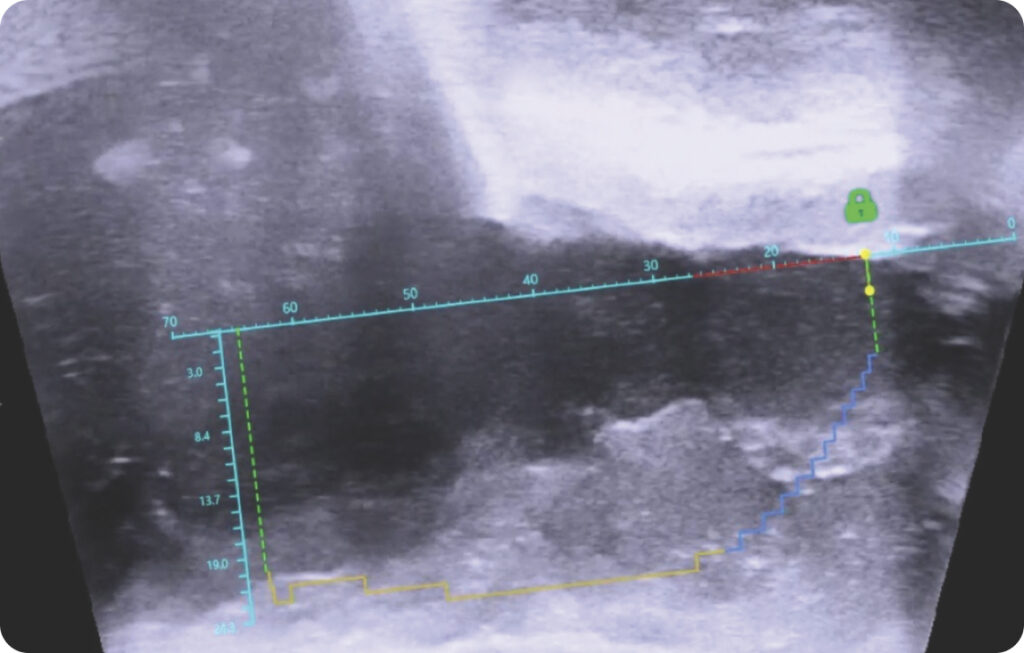

Personalized Treatment Planning

Computer-assisted planning allows the surgeon to maximize tissue resection while sparing the bladder neck, verumontanum, and external sphincter.